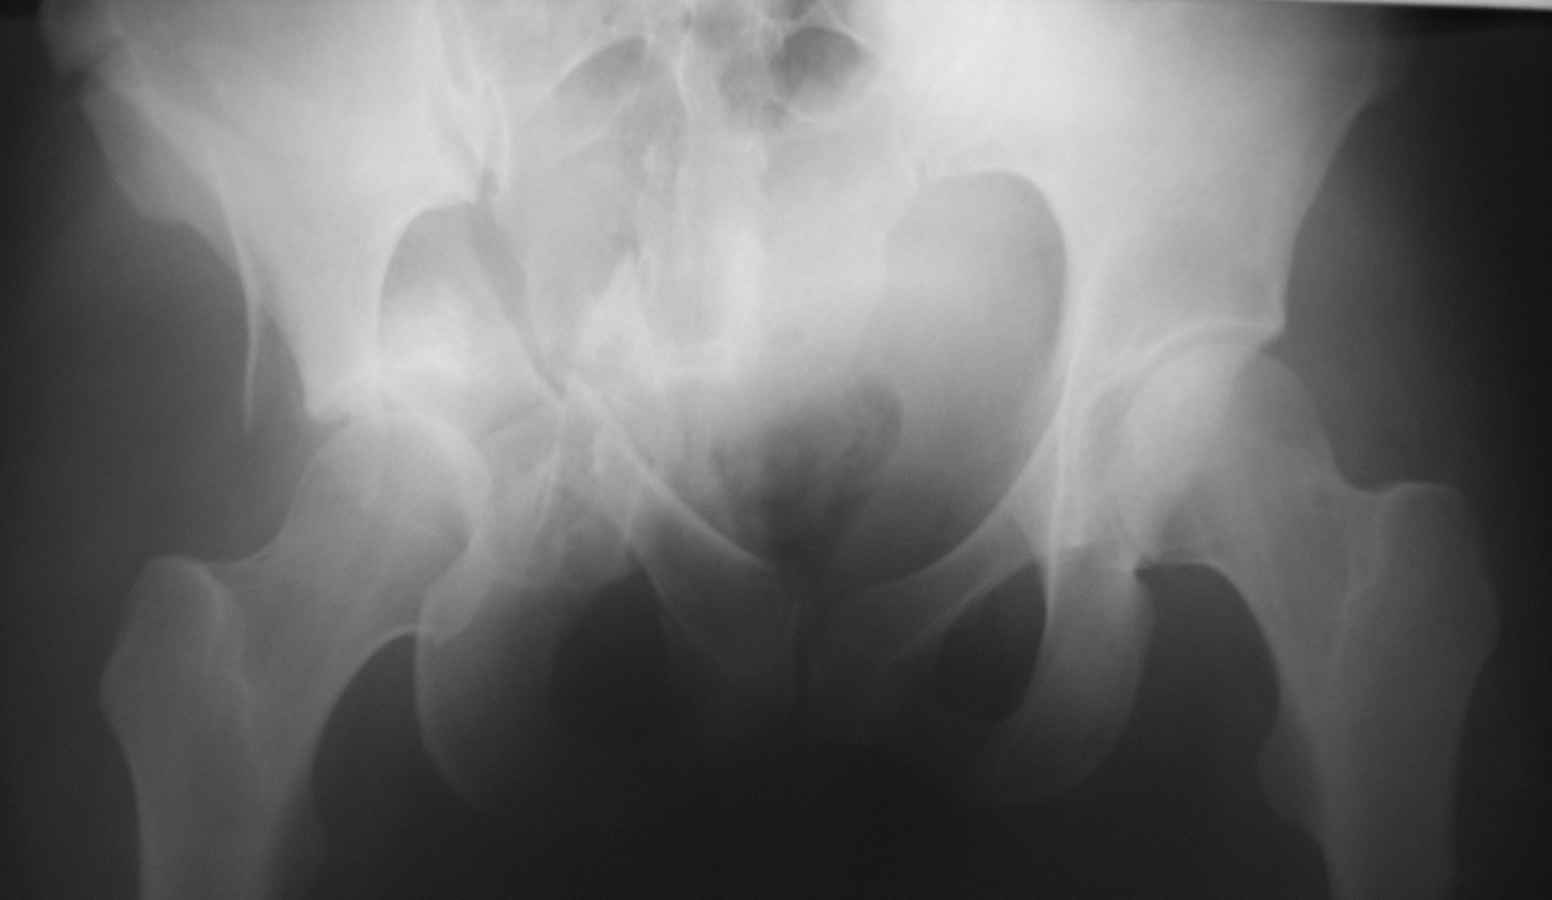

Уважаемые коллеги! Прошу вашего совета. Пациентке 28 лет. Травма в ДТП 13.11.10 - сбита автомобилем.

Первоначально было скелетное вытяжение, противошоковая терапия. Устранить центральный вывих в палате не удалось. 23.11 под наркозом на ортопедическом столе закрытое устранение центрального вывиха, снова наложено вытяжение. Сейчас - перед выбором, либо идти на открытое вмешательство и восстанавливать переднюю колонну, либо продолжить вытяжение до консолидации переломов с последующей костной пластикой и эндопротезированием.